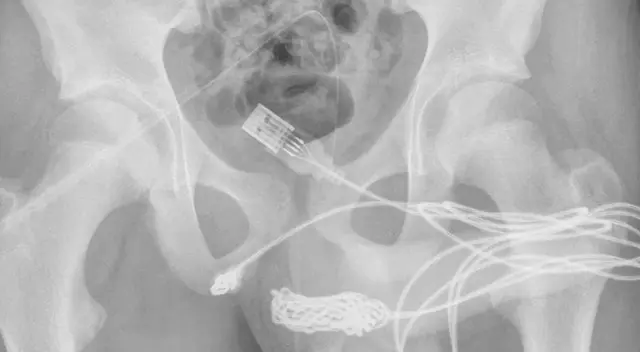

Según el informe médico publicado en la revista médica Urology Case Reports, el cable USB quedó atorado en el escroto del menor. Pese a los intentos por extraerlo por él mismo, el dispositivo se enredó por ambos lados alojándose en su uretra.

Las radiografías posteriores revelaron que había un verdadero nudo gordiano de cable USB dentro del adolescente, lo que requería que los cirujanos hicieran una incisión en la región entre los genitales y el ano para arrancarlo.